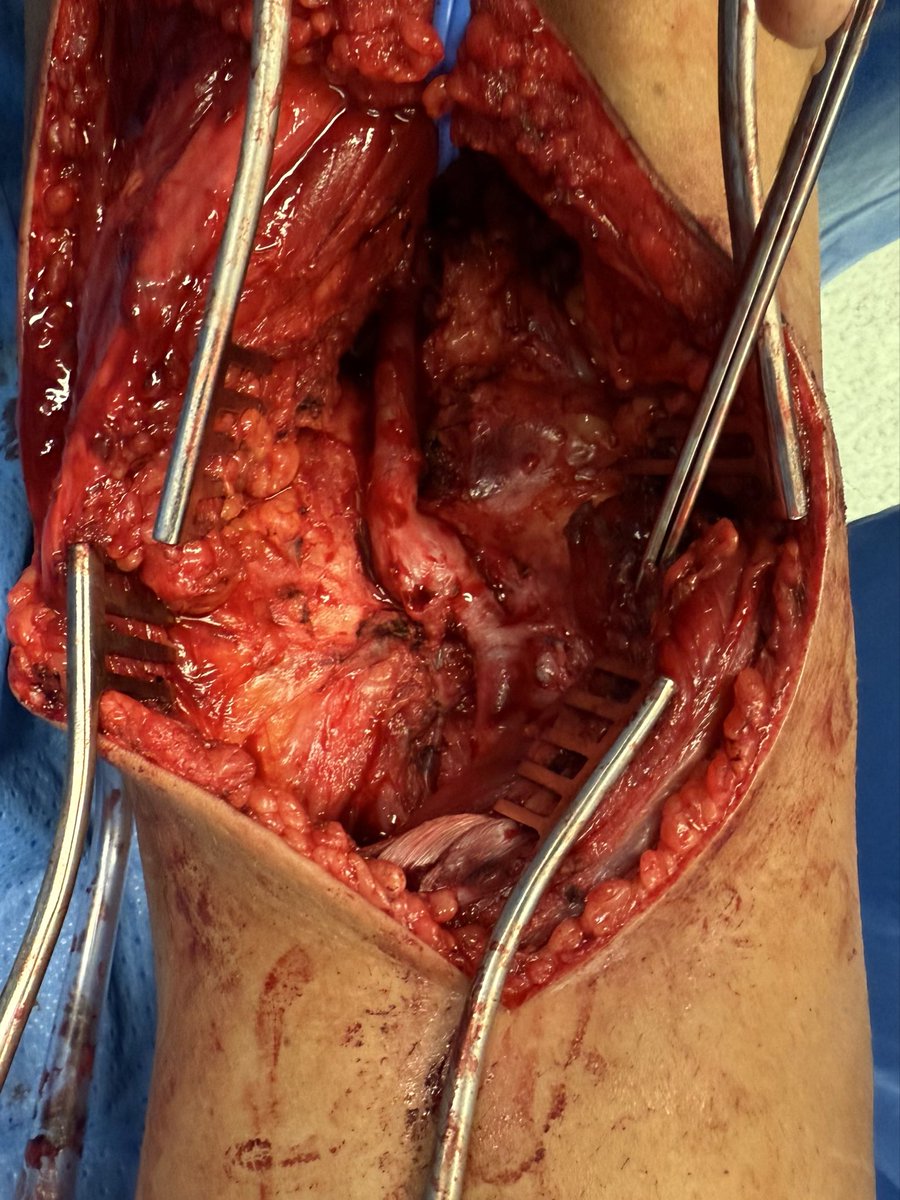

Diagnosis : Popliteal artery entrapment syndrome causing acute limb ischemia Intra-op pictures

#vasctwitter 17 yrs old male, keen football player.sudden onset pain in right leg and foot. Absent foot pulses and pale foot. CTA below. What is the diagnosis? Look at cross sectional image?! How would you treat?